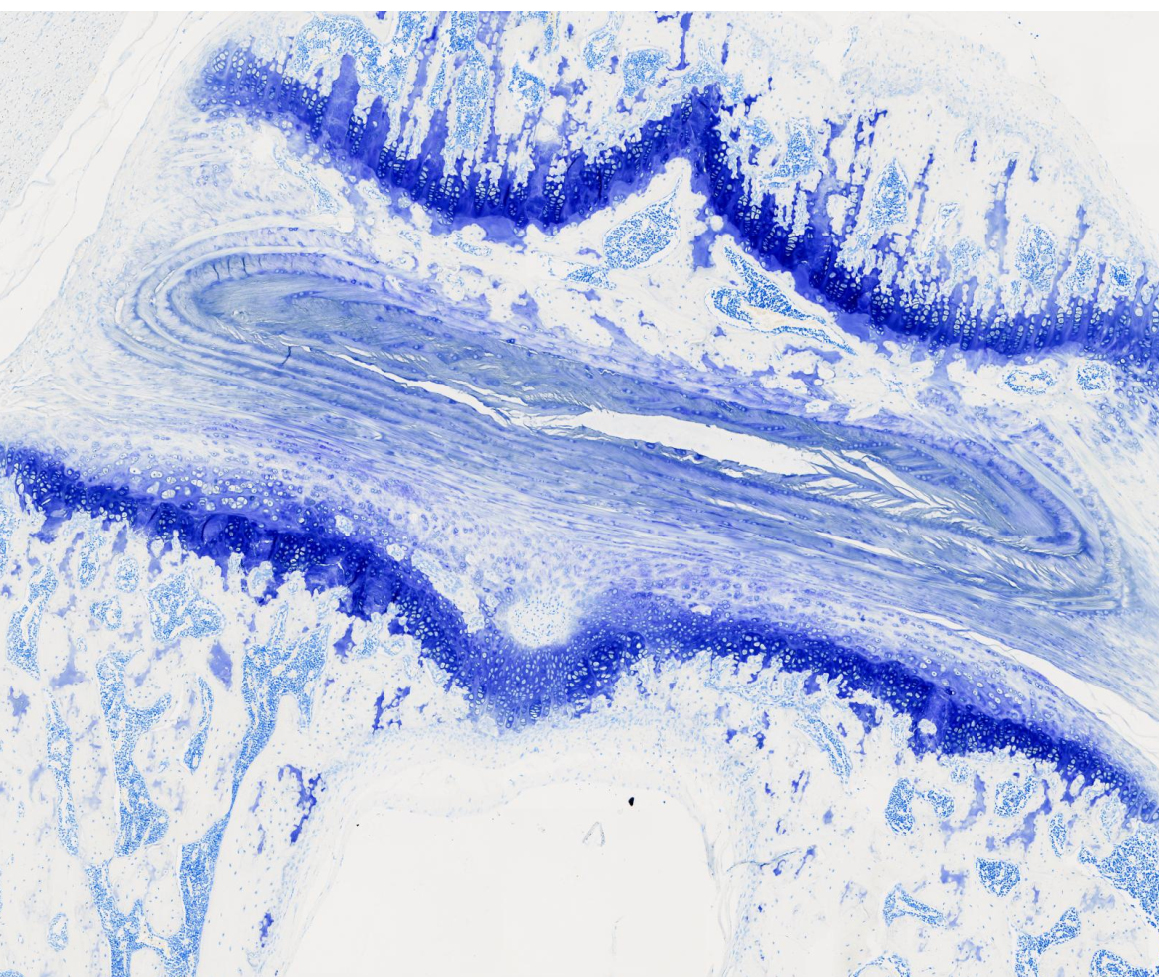

甲苯胺蓝

院校/单位:广州市粤斌医学研究有限公司

样本种属:大鼠

组织名称:

实验日期:2024-08-20